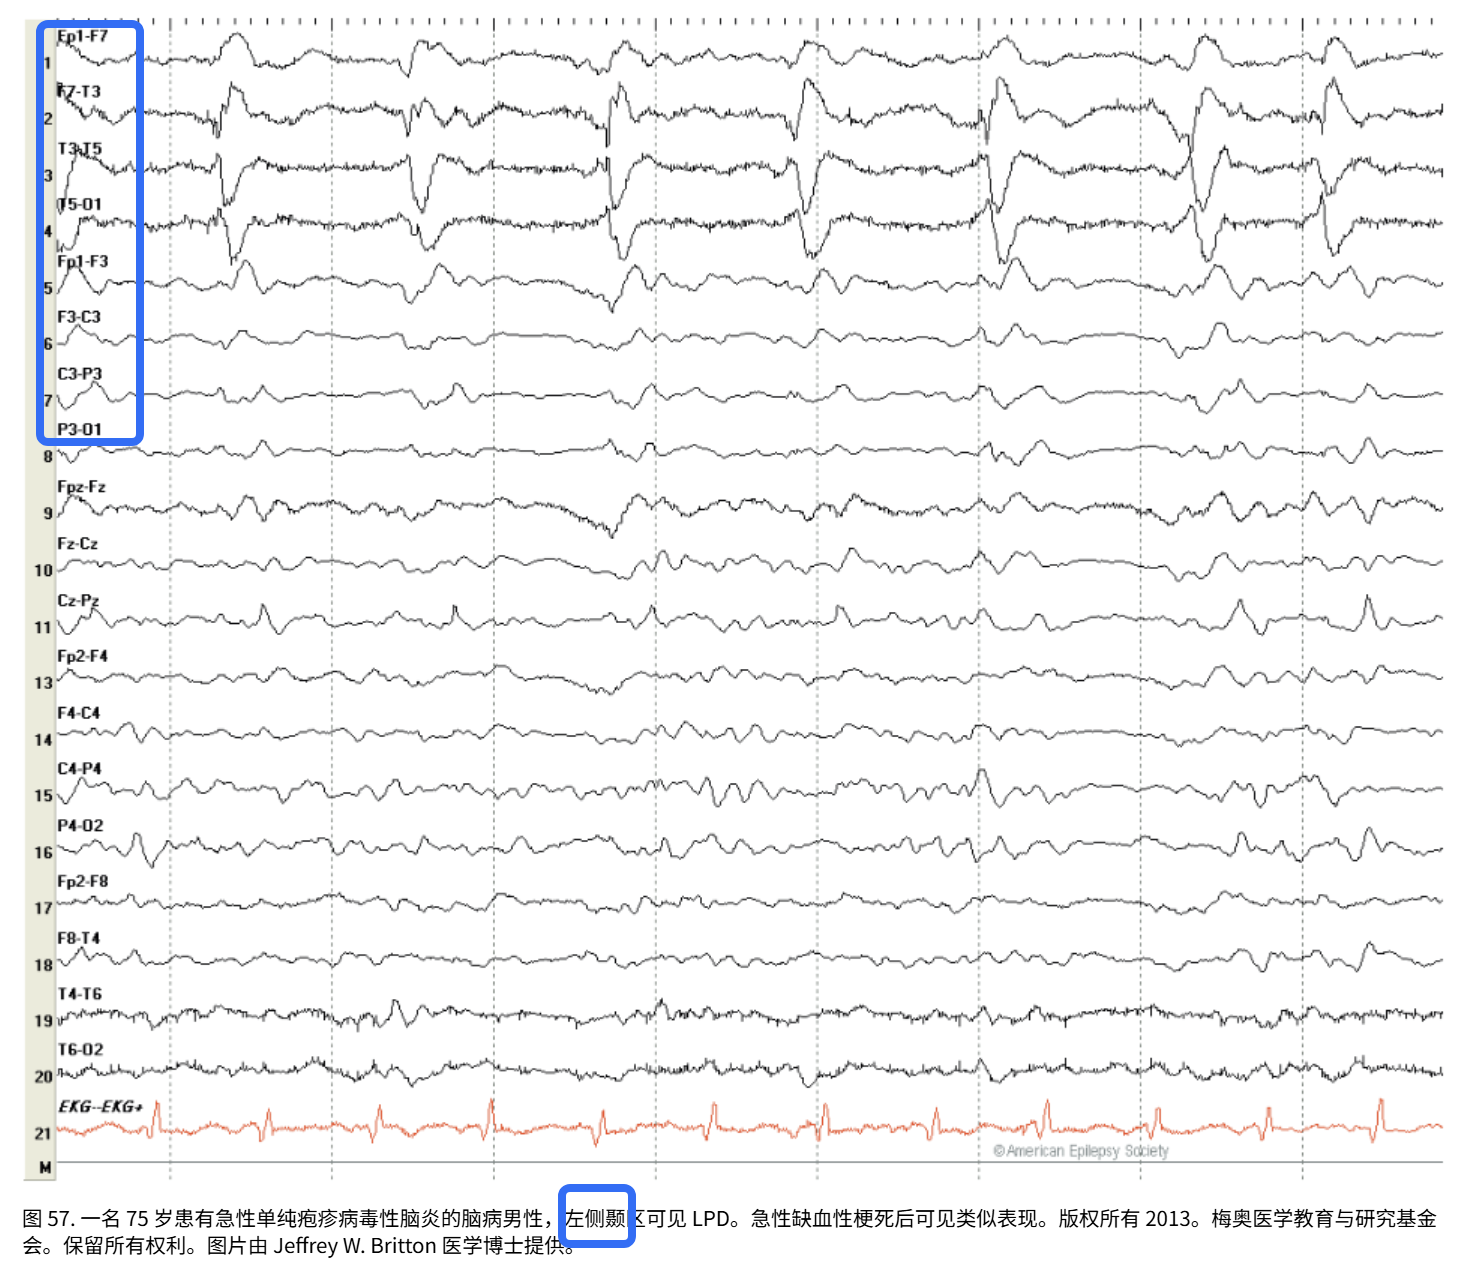

(2)单侧周期性放电:一侧大脑出现规律性放电

主要局限于一侧大脑半球。

在这里插入图片描述